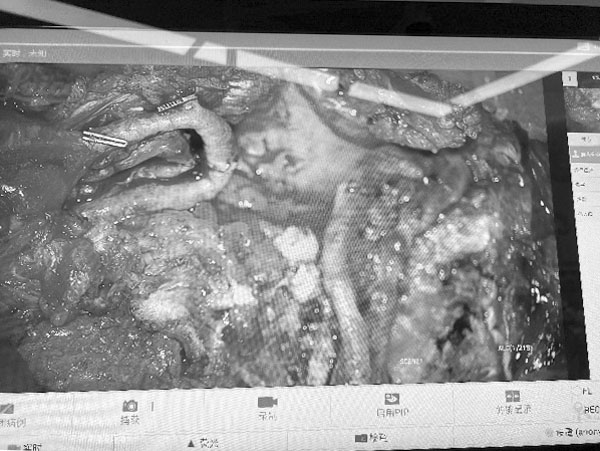

電子顯微鏡放大10倍后小血管的吻合

游離腹壁下動脈穿支皮瓣自體組織重建術(Deep Inferior Epigastric Perforator Flap,DIEP)是一種利用患者自身腹部皮膚、脂肪及血管進行乳房重建的顯微外科手術。該技術通過顯微外科手段將腹壁下動脈穿支血管與胸壁血管吻合,實現組織存活,具有創傷小、保留腹直肌功能的特點。其技術特點包括:在顯微鏡下完成精細血管吻合,確保移植皮瓣的血供;供區損傷小,僅切取腹部脂肪及皮膚,完整保留腹直肌結構,術后恢復更快;重建乳房形態自然持久,觸感與外形接近真實乳房,避免了假體相關的包膜攣縮等問題;同時實現腹部整形與乳房重建的雙重效果。

DIEP手術代表著自體組織乳房重建的技術高點,其核心在于顯微鏡下完成細小血管吻合,使離體皮瓣恢復供血并塑形為對稱的乳房形態。這一過程需以精準穩定的顯微外科技術為支撐,與整形外科理念實現深度融合,二者的協同,是操作成敗的關鍵。